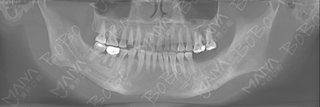

郭女士术前口腔ct全景片